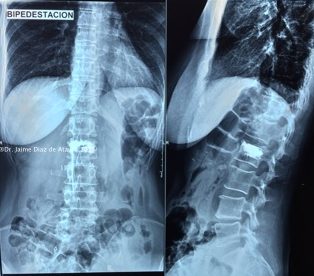

Diversos estudios clínicos y epidemiológicos han demostrado que existe correlación entre la deformación vertebral y problemas clínicos como la cifosis postraumática, que ha sido descrita como una de las deformidades postraumáticas potencialmente más graves. En este contexto, Vexim ha diseñado el implante SpineJack® para ofrecer al médico una solución totalmente controlada y completa para el tratamiento de las FVC, que permite primero una reducción anatómica y después una estabilización segura.

La operación es un procedimiento quirúrgico mínimamente invasivo (incisión pequeña) destinado a restaurar la forma inicial de la vértebra fracturada. Puede realizarse en una sala de radiología o en un quirófano, siguiendo unas normas muy estrictas de seguridad y asepsia.